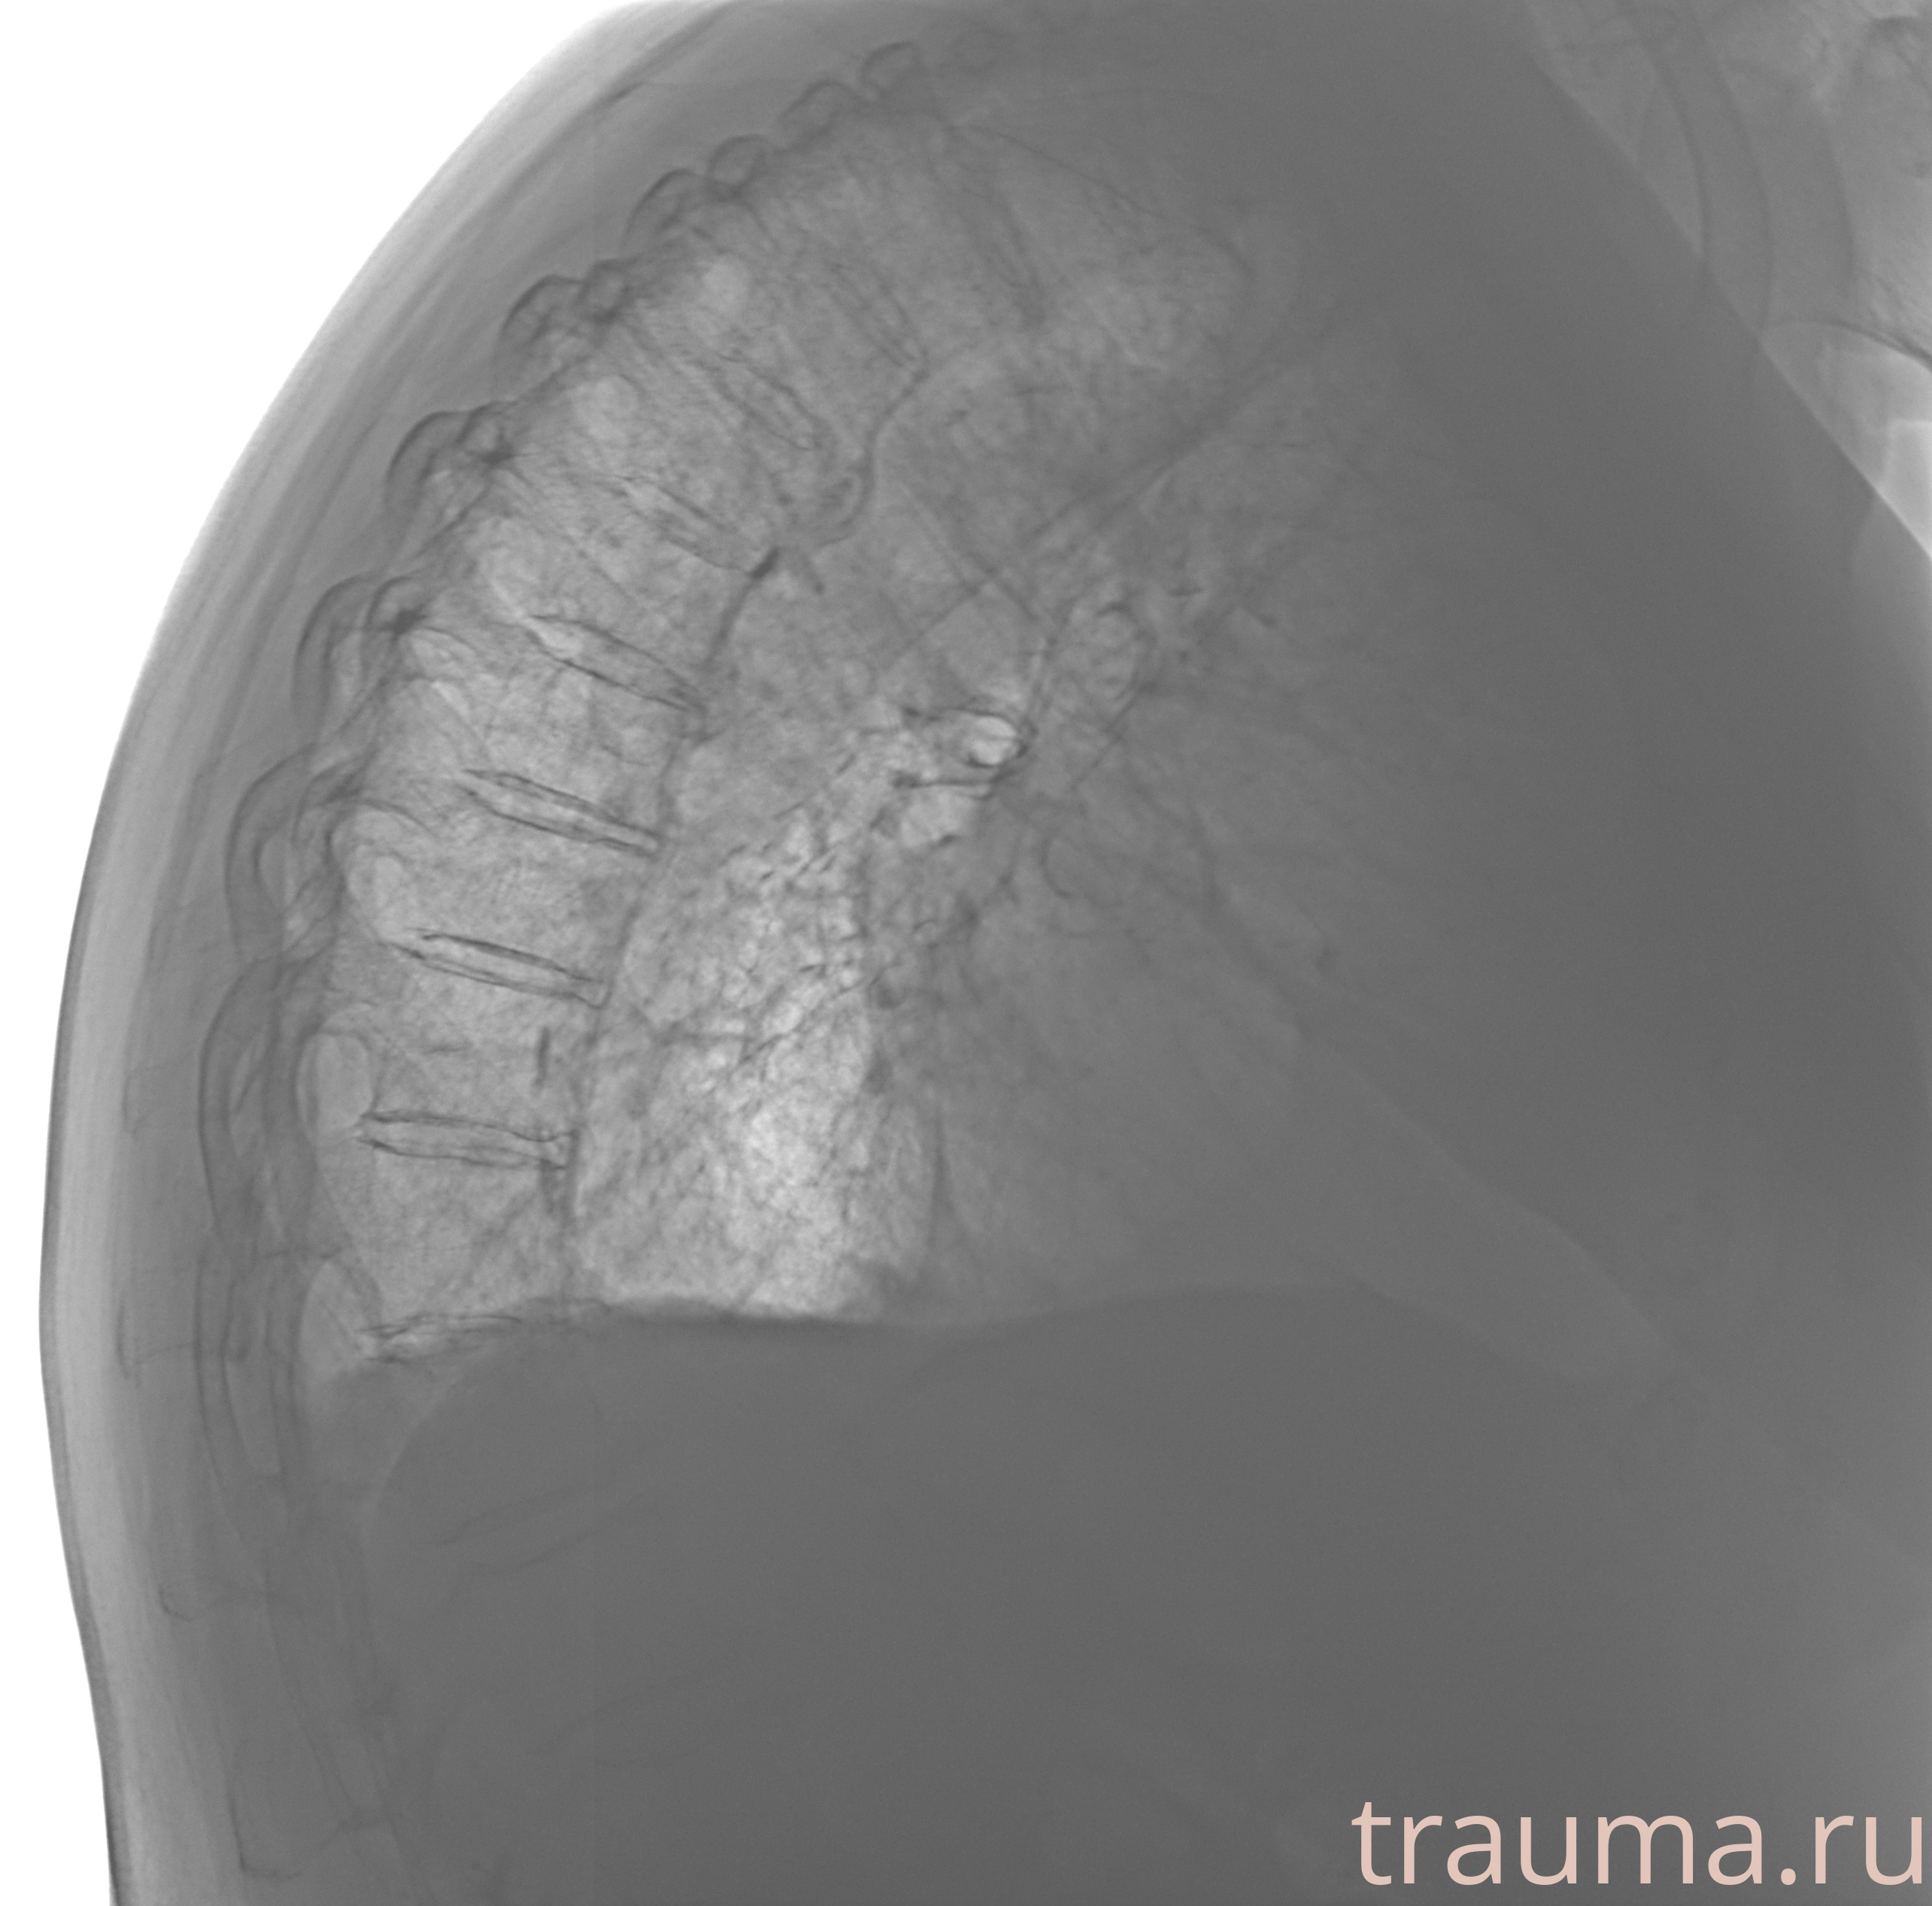

Рентгенограммы

Рентген на дому: по вашему адресу приезжает врач-рентгенолог, травматолог-ортопед с мобильным рентгеновским аппаратом, проводит диагностику травмы или заболевания, делает необходимые рентгенограммы, дает рекомендации по дальнейшему лечению. Получить качественные снимки в домашних условиях возможно благодаря уникальной методике, разработанной МосРентген Центром для института  Склифосовского